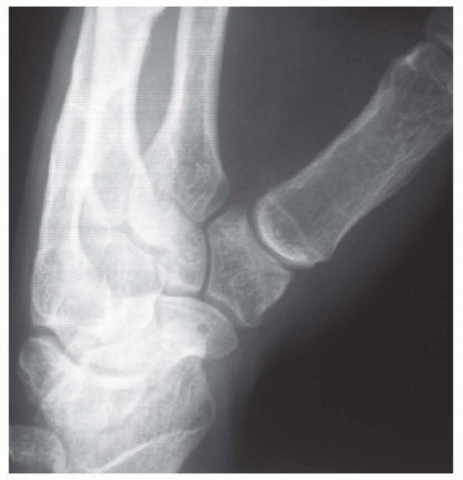

Our imaging protocol must be exhaustive to provide a three-dimensional understanding of the fracture morphology. Standard hand radiographs are insufficient due to the unique 30-degree pronated position of the thumb relative to the rest of the carpus. A True AP View of the Thumb CMC Joint (Robert's view) is obtained with maximal forearm pronation, placing the dorsum of the thumb flat on the cassette. This optimizes visualization of the joint space and the critical ulnar fragment. The True Lateral View (Billing and Gedda) is achieved with the hand pronated 20 degrees and the thumb flat on the cassette, with the X-ray beam tilted 10 degrees from vertical in a distal-to-proximal direction.

For complex, multi-fragmentary Rolando fractures, a Traction View under fluoroscopy is indispensable. Distraction at the CMC joint utilizes ligamentotaxis to help delineate comminuted fragments and assess the potential for closed reduction and percutaneous pinning versus the absolute need for open plating. Furthermore, when plain films inadequately delineate the spatial orientation of fracture fragments, particularly in Zone 2, a high-resolution Computed Tomography (CT) scan is strictly indicated. 3D reconstructions are invaluable for preoperative templating, allowing the surgeon to precisely map screw trajectories and select appropriate plate morphology before entering the operating theater.